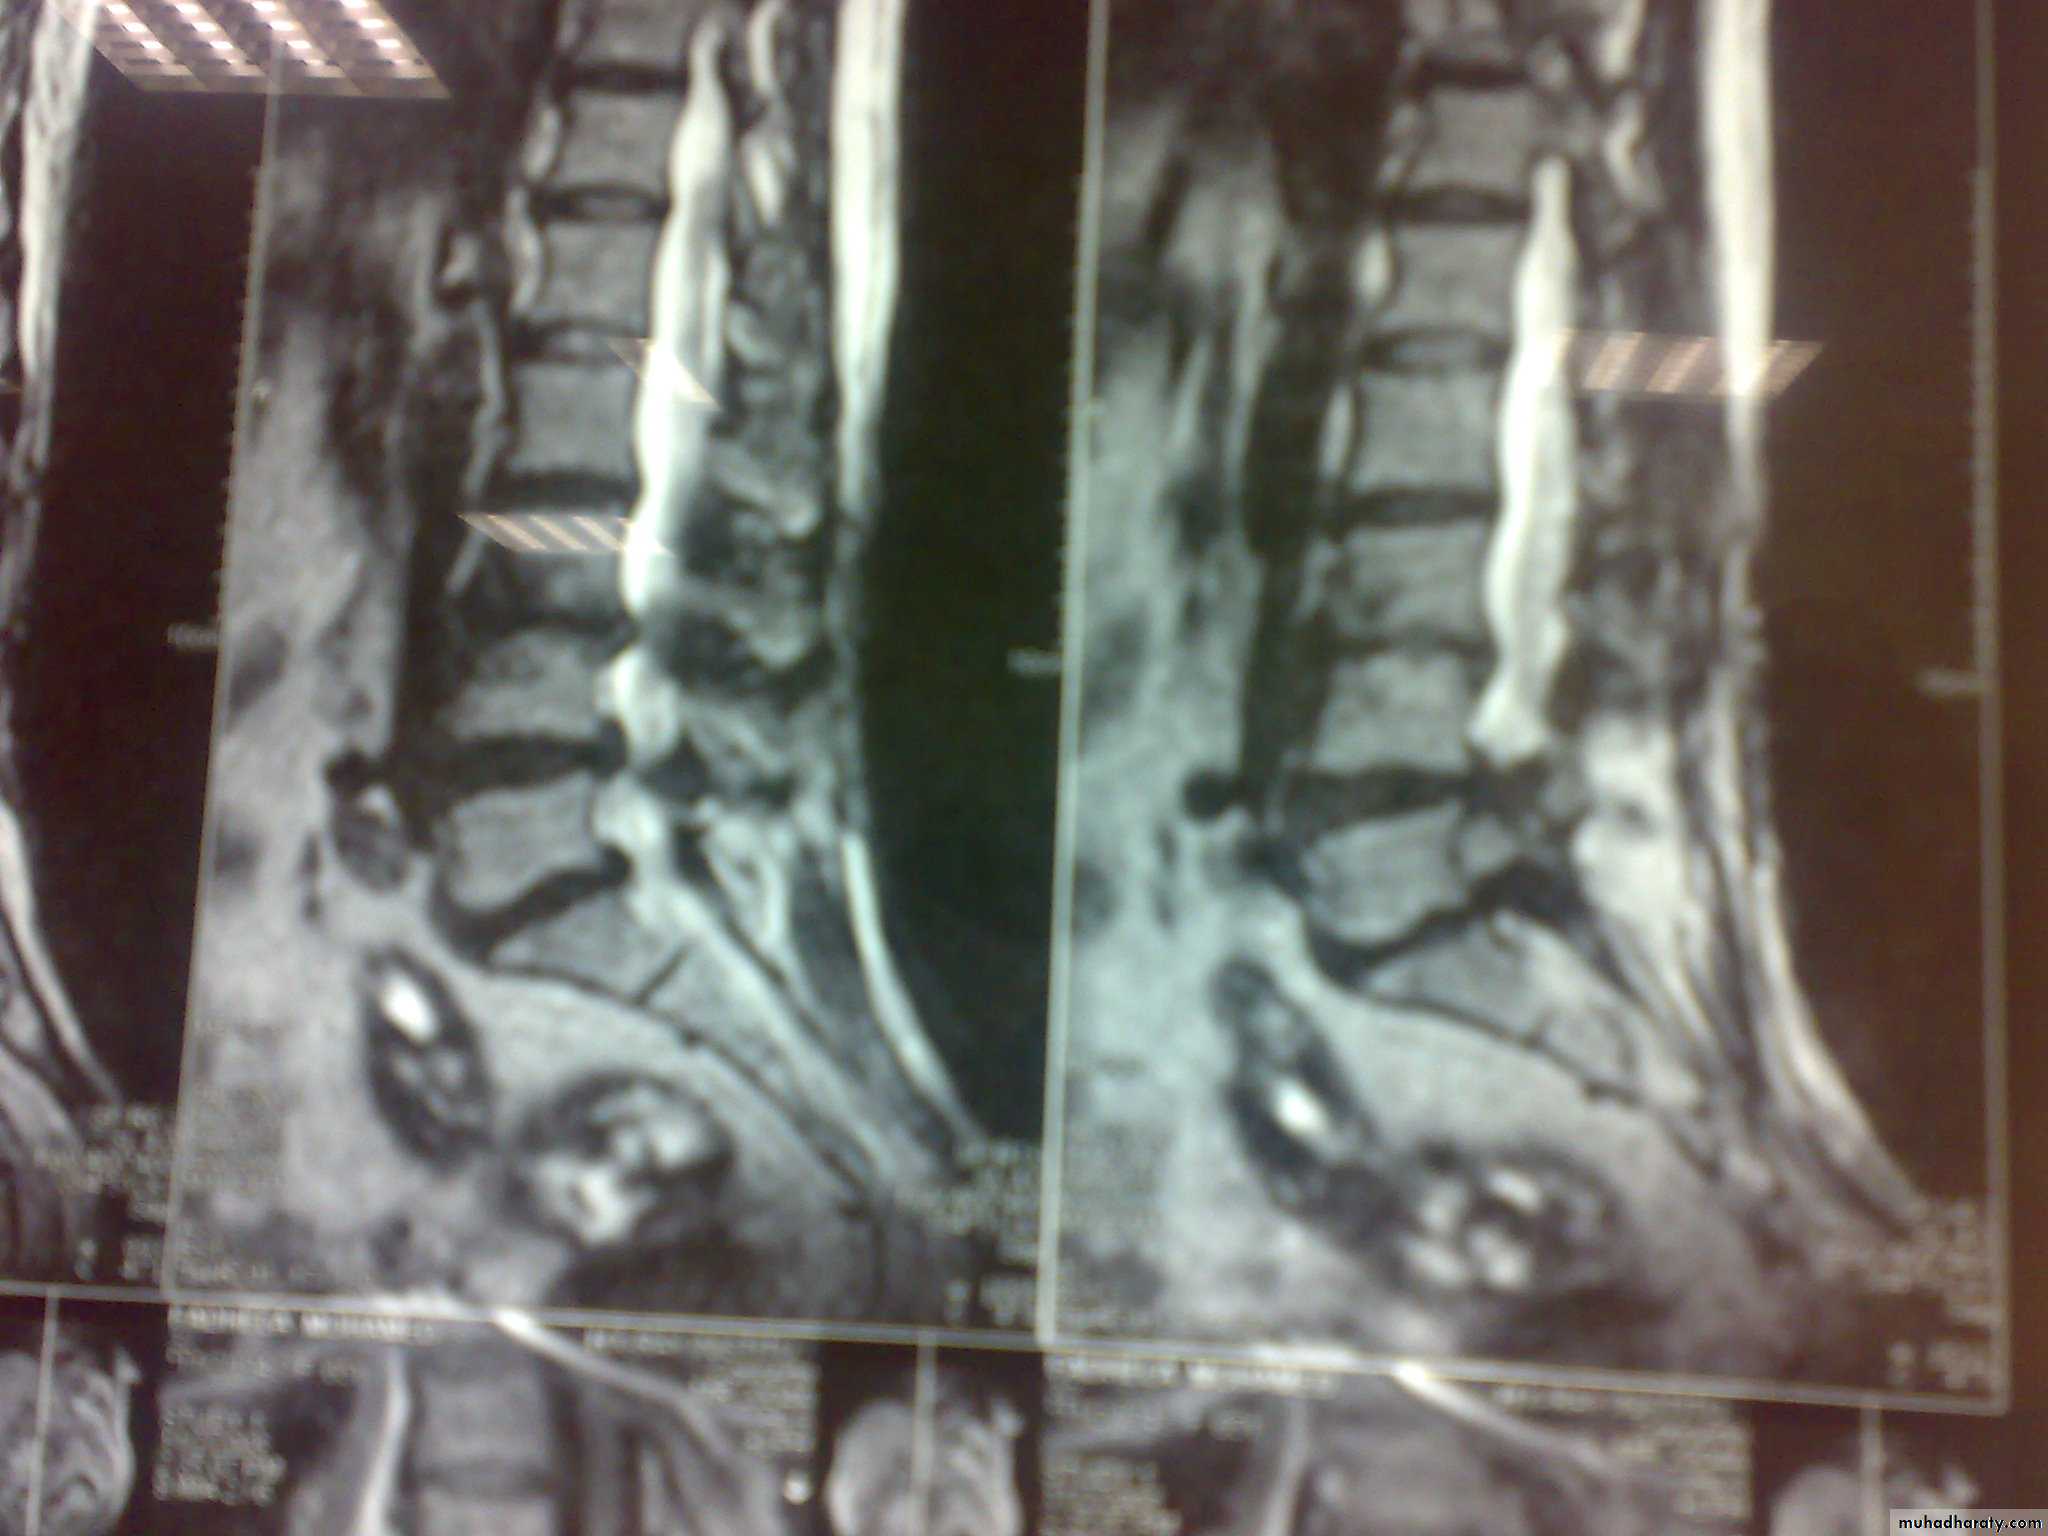

Discitis is an inflammation of the vertebral disc space often related to infection. Infection of the disc space must be considered with vertebral osteomyelitis, as these conditions are almost always present together and share much of the same pathophysiology, symptoms, and treatment. The lumbar region is most commonly affected, followed by the cervical spine and, lastly, the thoracic spineMRI with contrast before 1m.

MRI

Focal features are present in the majority of patients. 1-Musculoskeletal pain in the peripheral and axial skeleton (40 % of cases). 2-Discitis: more commonly involvesthe lumbar and lower thoracic vertebrae .-3-Septic arthritis:commonly affected the knee, hip,& sacroiliac joints, and the pattern either monoarthritis or polyarthritis.4-Osteomyelitis may also accompany septic arthritis.

INFECTIVE DISCITIS